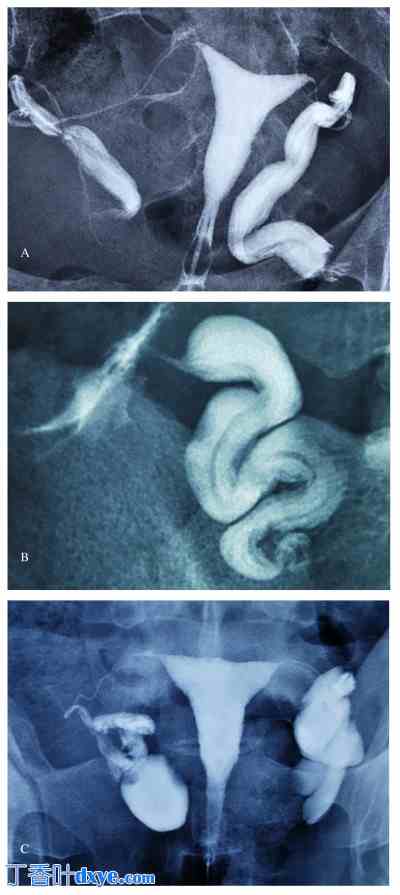

图 2。

a:双侧输卵管积水患者的子宫输卵管造影,患者可能从输卵管造口术中获益(输卵管内部结构保存完好);b. 包茎输卵管,输卵管皱褶保存完好。患者可能从包茎远端段扩张术中获益;c. 双侧输卵管积水患者的子宫输卵管造影,患者很可能需要输卵管切除术。